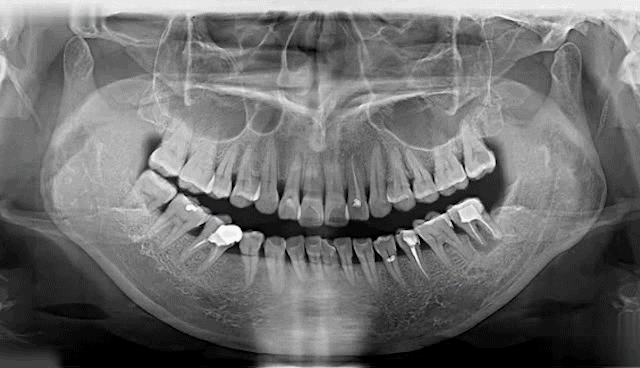

NO.1 缺牙的危害

牙齿缺失会引起邻牙松动、对牙伸长、引发牙周病,最终牙齿脱落等一系列问题,还会导致咬合紊乱、咀嚼功能变差,甚至影响身体健康。